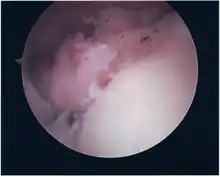

SLAP Tear

Arthroscopic SLAP Lesion (type 2) repair

Following inspection and determination of the extent of injury, the basic labrum repair is as follows.